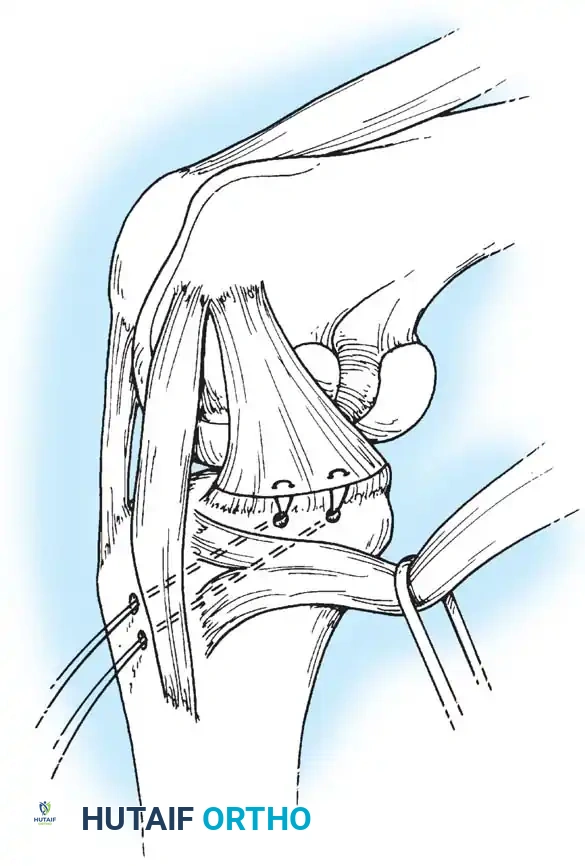

Deep capsular tears are repaired with interrupted sutures. If the LCL or popliteus is avulsed from the lateral femoral epicondyle, anatomical footprints are identified, and the structures are repaired using suture anchors. Tensioning must be performed with the knee in 30 degrees of flexion and neutral rotation.

Image

In cases where the native tissue is non-viable or the injury is subacute, an anatomical posterolateral corner reconstruction using an autograft or allograft (e.g., Achilles or semitendinosus) is mandated. The graft is routed to recreate the LCL and popliteofibular ligament.